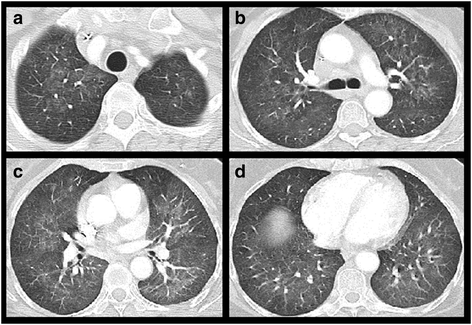

Pneumocystis jirovecii pneumonia. Patient with adjuvant chemotherapy for breast cancer. Chest CT at the level of the lung apex (a), tracheal bifurcation (b), apical segments of the lower lobes (c) and the dome of the right diaphragm (d) at lung windows: Diffuse, symmetrical, bilateral ground glass sparing the lung periphery both in the axial plane as well as lung apices and bases